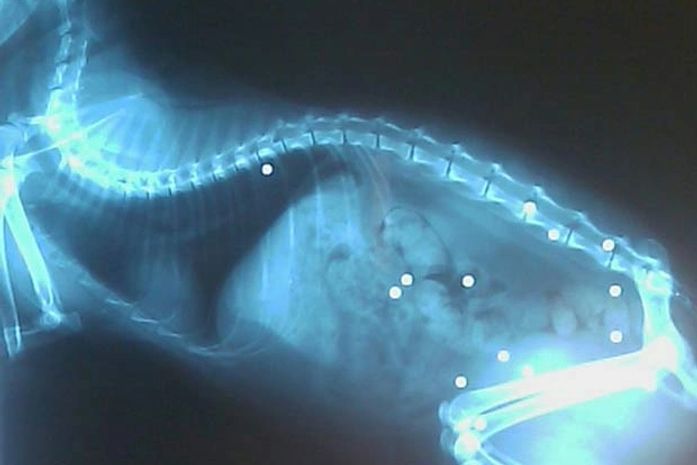

Segundo a emissora de TV "WISH", os donos avisaram a polícia depois que notaram que o gato chamado "Rubix" apresentava várias feridas. O felino foi levado a uma clínica veterinária, onde um raio-x mostrou que ele tinha 19 marcas de tiros de chumbinho pelo corpo.